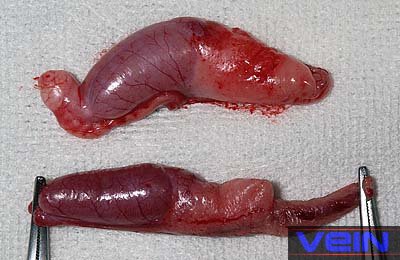

Az anya nyulaknál ivartalanítás ajánlott. Az azonban fontos,

hogy stabilizálják az állatokat az operáció előtt.

A kezelés magában foglalja az antibiotikumok

adását, és a folyadék terápiát. A méh eltávolítása során mintákat kell gyűjteni a bakteriális kultúrához, és az antibiotikum

érzékenységet meg kell határozni. A műtét